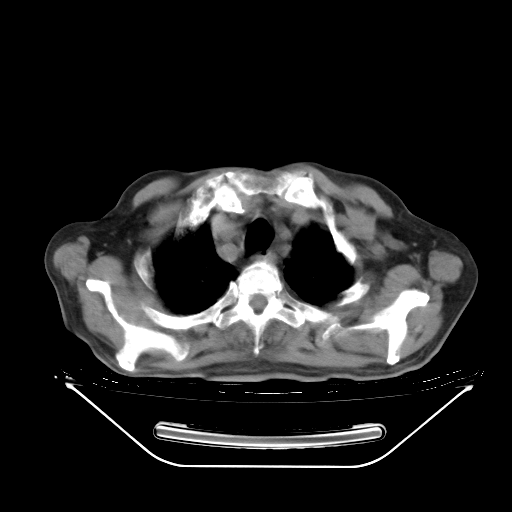

今天复查肺部CT,发现双肺广泛磨玻璃样改变。所以我把3月19日和5月9日相隔50天的肺部CT上传。请大家会诊。

5月9日肺部CT(在4月27日齐鲁医院肺部CT描述部分肺组织磨玻璃样改变,12天后肺组织广泛磨玻璃样改变)

2009年5月9日肺部CT

大致读了系列胸部CT:纵隔窗无明显异常,肺窗:从4、27至今:主要是双肺中下野外带可见毛玻璃样改变,目前处于急性肺泡炎阶段,至于原因考虑1、结替组织或胶原血管性疾病所致?2、恶性疾病如恶组在肺部所致的表现或细支气管肺泡癌?3、药物或其它原因如肺蛋白沉着症所致肺泡炎目前不太可能?总之,明天就去请我院的呼吸科、感染科、血液科和临免专家会诊哈。